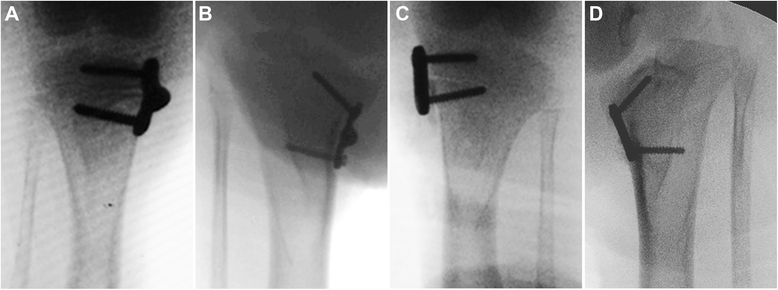

试验组:动物被放置于可仰卧位的桌子上。胫骨近端的内侧面进行2-3厘米长的切口,进行胫骨深部分离,保存骨膜。在中冠状面,1mm的Keith针插入到长骨体生长部。这个过程在荧光镜下进行,铰接板被放置。1.8-mm钻头钻孔以减少螺钉置入过程中的应力。螺钉应平行或稍微收敛(0°至20°),而不侵犯生长板软骨。两个螺钉交替拧紧。

术后护理:术后立即通过正位透视图像评估内侧斜坡角(MSA),即垂直于胫骨解剖轴线和胫骨内侧平台切线的夹角、胫骨近端内侧角(MPTA,胫骨解剖轴线与胫骨平台内侧角和外侧角之间线的夹角),和两个臂的角度(ATA)。术后6, 12,18周进行摄片。最后造影后立即处死动物,除去植入物。获取骨骺与干骺端骨膜和软骨膜下的种植体以及邻近骺板和干骺端。样品用10%福尔马林固定,并嵌入甲基丙烯酸甲酯。在额状面上,样品被切割成段,切片7-mm厚,用番红O-快绿染色。

样品的测量:所有测量均以盲法进行。测量是由两个作者独立进行的,并用两个测量的平均值进行分析。使用Kanellopoulos等人描述的方法评估半骨骺。在前后正位X线片,测量三个角度,即,MSA,MPTA,和ATA。用X-射线衍射测定干骺端螺纹孔边缘的残余应力。钛合金反射是在2theta= 70.631。在六个位置测量晶格应变。组织学研究,在40?×?每个部分放大图像下测定软骨膜组织的板和骨骺中心之间的宽度。